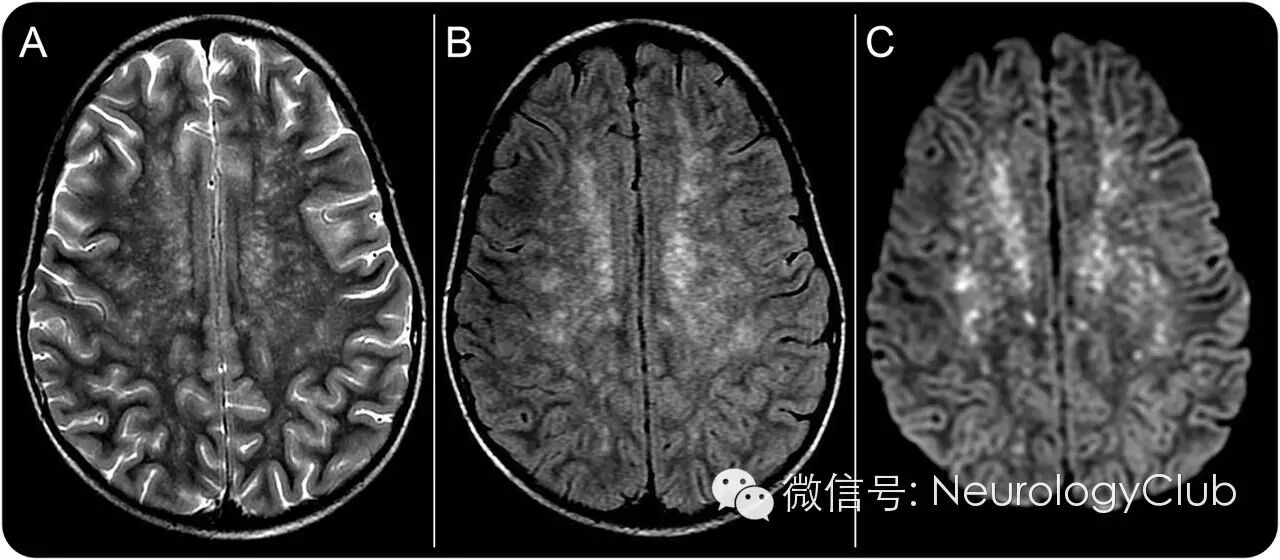

7岁女孩,既往体健,因高热、头痛及弥漫瘀点状皮疹就诊。血清学证实为落基山斑疹热,一种由立克次体感染引起的蜱媒传染病。微生物通过血行播散至中枢神经系统,主要累及小动脉和毛细血管,导致炎症及血脑屏障的破坏。MRI上典型表现包括继发于血管炎的脑室旁和皮质下梗死,多分布于血管周围,出现满天星样表现(图)。尽管在一定的临床背景下有高度提示意义,但相似的影像学改变也可见于其他病毒、细菌、真菌和寄生虫感染。

(A:T2WI;B:FLARI;C:DWI;双侧半卵圆中心点状高信号,呈满天星样改变,符合落基山斑疹热导致的多发沿血管周围分布的急性梗死)